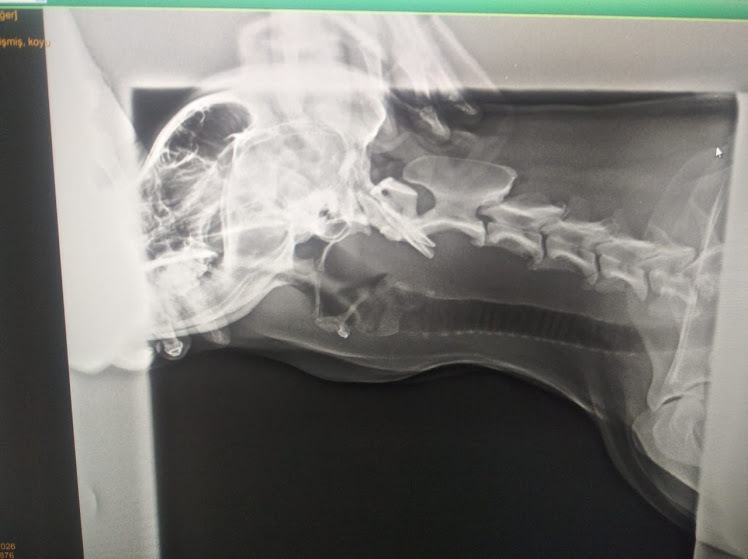

Обследование - 10 манат, рентген - 25 манат. Про хирургическую операцию и спрашивать не стали.

У собаки на шее обнаружилась опухоль. Рентген подтвердил, но врачи не знали происхождение опухоли. Может там в пищеводе застрял мячик, проглоченный псом, или плотное мясо, мешающее собаке глотать. Еще была версия опухоли после ангины, которой собака действительно недавно болела.

Выяснить причину утолщения можно в ходе операции, но врач сказал, что не уверен в благополучном исходе. Против операции выступили мы - хозяева. Доктор массировал опухоль рукой, наверное надеясь вытолкнуть в пасть собаки то, что может быть, застряло. Но псу стало больно и он вежливо отошел от врача, поскулив от боли.

Собаке нужно было провести процедуру осмотра пищевода через тонкий шланг с камерой на конце, но этого оборудования в клинике не оказалось.

Последняя информация настроила меня на оптимизм. Мы решили на этом завершить наш визит врачам. Дамы на рецепшин помогли нам отправить по телефонам рентгеновские снимки другому доктору, вообще были очень любезны, но пять манат вернуть мне сдачу с 40 манат (вся услуга - 35 манат) у них не нашлось. Взять пять манат они отказывались, а что делать, арестовать нас здесь потому, что в кассе нет разменных денег? Решили, что если опять сюда приеду, эти пять манат мне зачтутся.